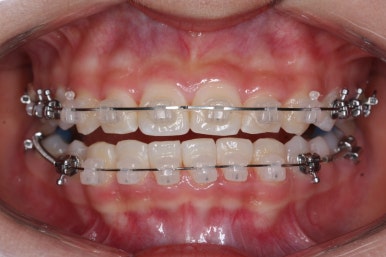

치료 종료 후의 모습입니다.

치아들이 가지런하게 되었고, 나오지 못하던 치아도 잘 나와서 가지런해졌습니다.

해당 부위 앞뒤로 쓰러져 있던 치아들도 축이 바로 잡혔고, 자연스레 위-아래 치아의 중앙선도 맞아졌습니다.

얼굴 모습의 큰 변화 없이 양호한 모습 그대로 마무리가 되었고, 웃을 대 위아래 치아의 중앙이 안맞았던 부분도 개선되었습니다.

치아가 잘 올라온 것을 볼 수 있습니다.